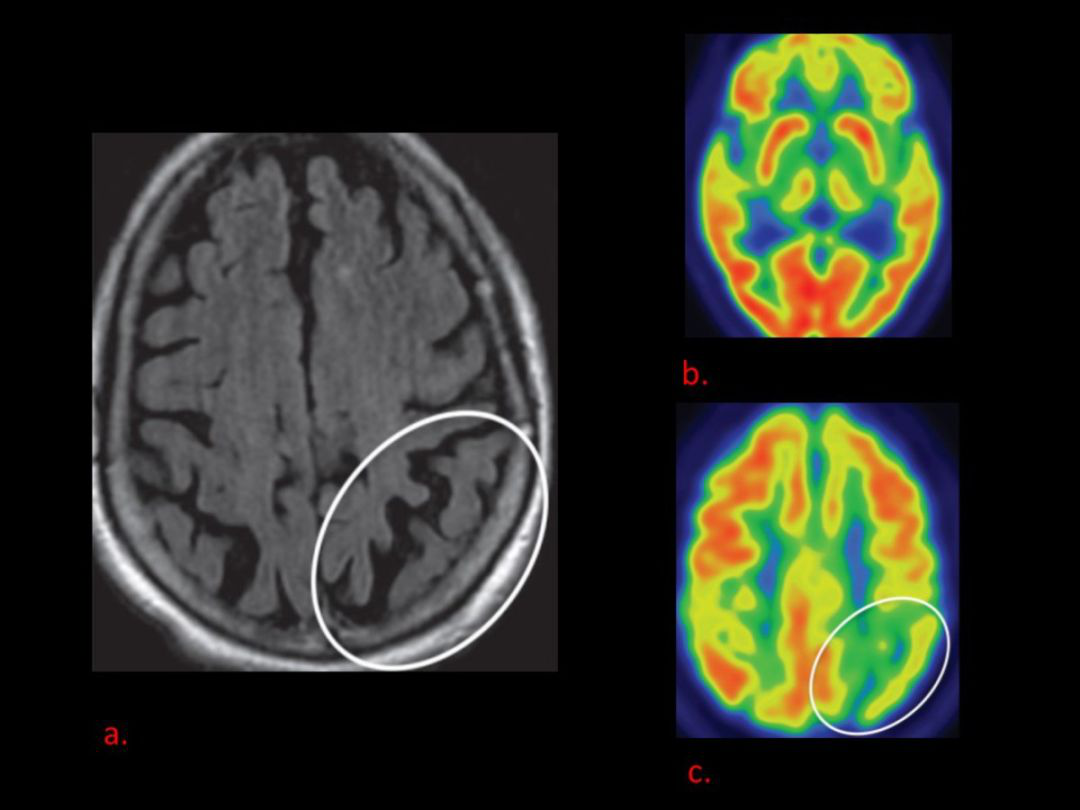

DLB 的 MR 表现:缺乏非特异性,如轻度广泛性萎缩,颞叶内侧通常被保留。MRI 主要的主要目的是排除其他原因引起的痴呆。典型表现为枕叶(包括视觉皮层的低代谢)。

枕叶(包括视觉皮层的低代谢)

严重的双侧前额叶、顶叶、颞叶和后扣带回-丘脑前皮质低代谢,以及枕叶包括初级视觉皮层的低代谢

CBD 的 MR 表现:早期可正常或脑萎缩(以额顶叶萎缩为主),FDG-PET 皮层代谢减低。

顶叶萎缩伴皮层代谢减低